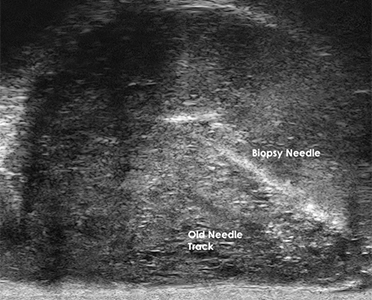

The 29 MHz ExactVuTM system facilities resolution down to 100 microns – and enables

detailed visualization in real-time of the prostate anatomy and characterization of

the prostatic tissue.

The following are select cases that are routinely derived from the ExactVuTM

micro-ultrasound platform and verified with pathological results.